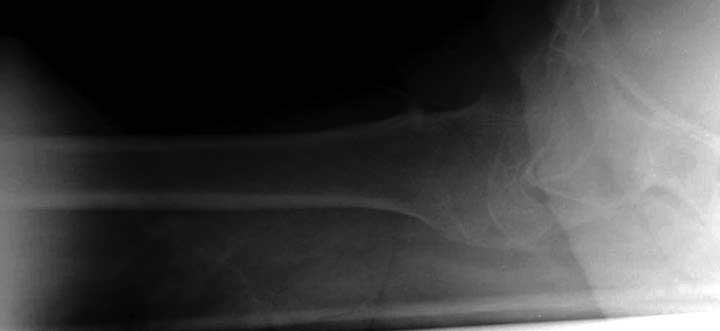

Первые снимки показывают технические погрешности установки DHS. Не была достигнута репозиция, конечность в флексии и шейка в ротации. Сегодня все меньше обращают внимание на параметры для оценки репозиции (S контуры Lowell в обеих проекциях и Garden Alignment Index, в норме 155 и 180 градусов), хотя такие простые тесты помогли бы дорепонировать смещение. Винт находится сзади в головке, что при нагрузке поменяет вектор и вместо компрессии в линии перелома срежет головку-Cut Out!